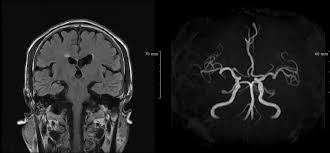

MRI(자기 공명 영상)은 강력한 자기장과 라디오파를 이용하여 체내 조직의 이미지를 생성하는 기술입니다. MRI는 연부 조직, 즉 뇌, spinal cord, 근육, 그리고 다양한 내장 장기 등을 상세하게 볼 수 있는 특징이 있습니다. 주로 신경계, 근골격계 및 종양 연구의 진단 도구로 사용됩니다.

반면에 MRA(자기 공명 혈관 영상)는 MRI의 일종으로, 혈관의 이미지를 생성하는 데 초점을 맞추고 있습니다. 이는 혈관의 구조 및 흐름을 평가하는 데 유용하며, 주로 심혈관 질환의 진단에 사용됩니다. MRA는 특히 혈관의 협착이나 막힘, 동맥류와 같은 혈관 관련 문제를 발견하는 데 매우 유용합니다.

MRA는 MRI의 기법을 기반으로 하므로, 기본적으로는 동일한 작동 원리를 가지고 있지만, 약간의 차이점이 있습니다. MRA는 특히 혈관을 시각화하는 데 최적화되어 있으며, 주로 조영제를 사용하여 혈관을 더욱 뚜렷하게 구분합니다. 조영제는 혈관 내에서 신호의 차이를 만들어 신호 강도를 높여줍니다. 이로 인해 혈관의 형태와 상태를 더욱 명확하게 시각화할 수 있습니다.

그러나 MRA의 단점으로는 조영제를 사용해야 하는 경우가 많아서 일부 환자들에게 알레르기 반응을 일으킬 수 있습니다. 또한, MRA는 혈관의 구조를 잘 보여주지만, 인근 연부 조직에 대한 정보는 제한적이기 때문에 경우에 따라 MRI와 병행하여 사용해야 할 필요가 있습니다.